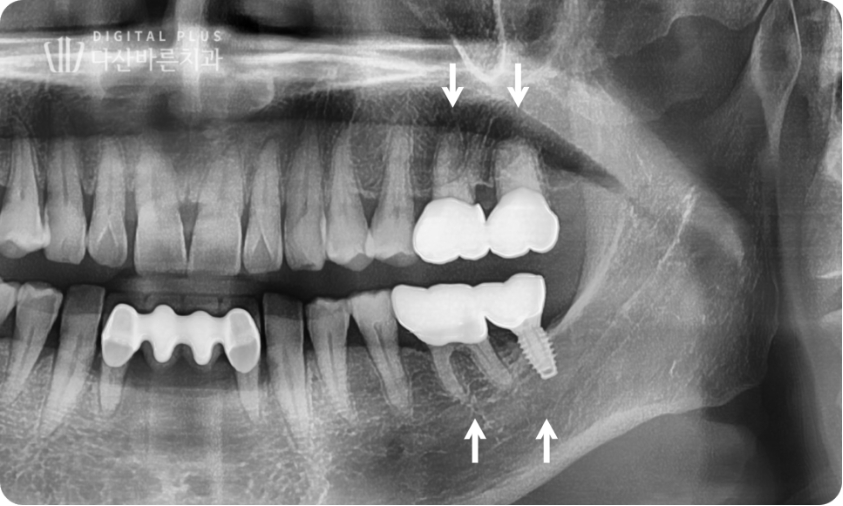

▲ 아래 빠진 치아 임플란트 치료 & 위쪽 정출 치아 크라운 치료 완료.

정출된 치아를 크라운 치료로 진행하는 경우,

치아가 정출된 부분만 살짝 삭제한 뒤 크라운을 씌워 치료를 마무리하게 되는데요.

추가적인 정출을 방지하기 위해 맞은편 빠진 치아 자리는 반드시

임플란트로 공간을 메워줘야 합니다.

▲ 치료 완료 후 구강 사진(좌측).

충치가 있었던 인접치들까지 깔끔하기 치료한 뒤 최종적으로 치료가 마무리됐는데요.

정출된 치아로 무너진 교합과 치아 배열까지 깔끔하게 정리된 모습입니다.